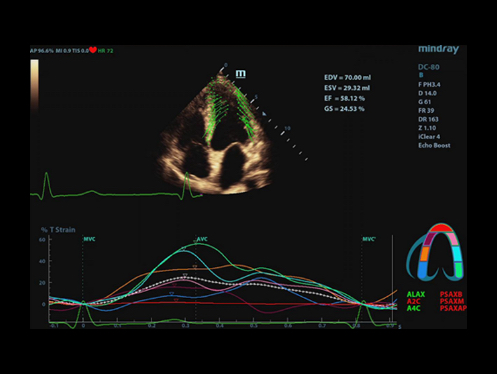

eXceptional intelligence

Kecerdasan di seluruh alur kerja yang ada

Untuk meningkatkan efisiensi pemindaian dengan akurasi dan konsistensi yang lebih tinggi, X-Insight memberikan kecerdasan luar biasa di seluruh alur kerja ujian, mulai dari akuisisi pesawat hingga pengoptimalan gambar, dan dari penghitungan hingga protokol ujian.